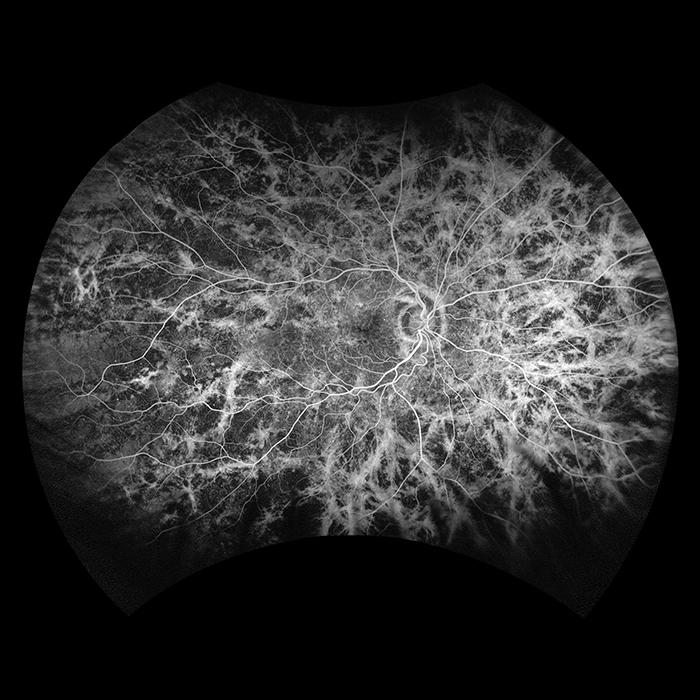

Optos introduced ultra-widefield (UWF™) retinal imaging to enable eyecare professionals to discover, diagnose, document and treat ocular pathology that may first present in the periphery - pathology which may go undetected using traditional examination techniques and equipment. Our UWF, high-resolution retinal imaging devices each image more than 80% or 200˚ of the retina in a single shot. Our complete list of ultra-widefield retinal imaging devices is below.

Silverstone RGB is redefining excellence in retinal imaging. It is the only device that captures true color, 200° optomap ultra-widefield images in a single shot, seamlessly integrated with guided swept-source OCT. For the first time, eye care professionals can access nine powerful imaging modalities in one system, each designed to image pathology anywhere in the retina.

optomap has been shown to enhance pathology detection, disease management, and to improve clinic flow. Now with nine retinal imaging modalities, including integrated, peripheral Swept Source OCT, Silverstone RGB facilitates examination of the retina from vitreous through the choroidal-scleral interface.

California was developed for medical imaging and is a standard for retinal screening programs. California is available in multiple models with multiple imaging modality options. California produces a 200°, single shot retinal image of unrivaled clarity in less than ½ second and is changing the management of diseases including Geographic Atrophy, Diabetic Retinopathy, AMD, and Uveitis.

Daytona produces a 200° single shot optomap retinal image of unrivaled clarity in less than ½ second. This fast, easy, patient-friendly, ultra-widefield imaging technology was designed for healthy eye screening and has been shown to improve practice flow and patient engagement.